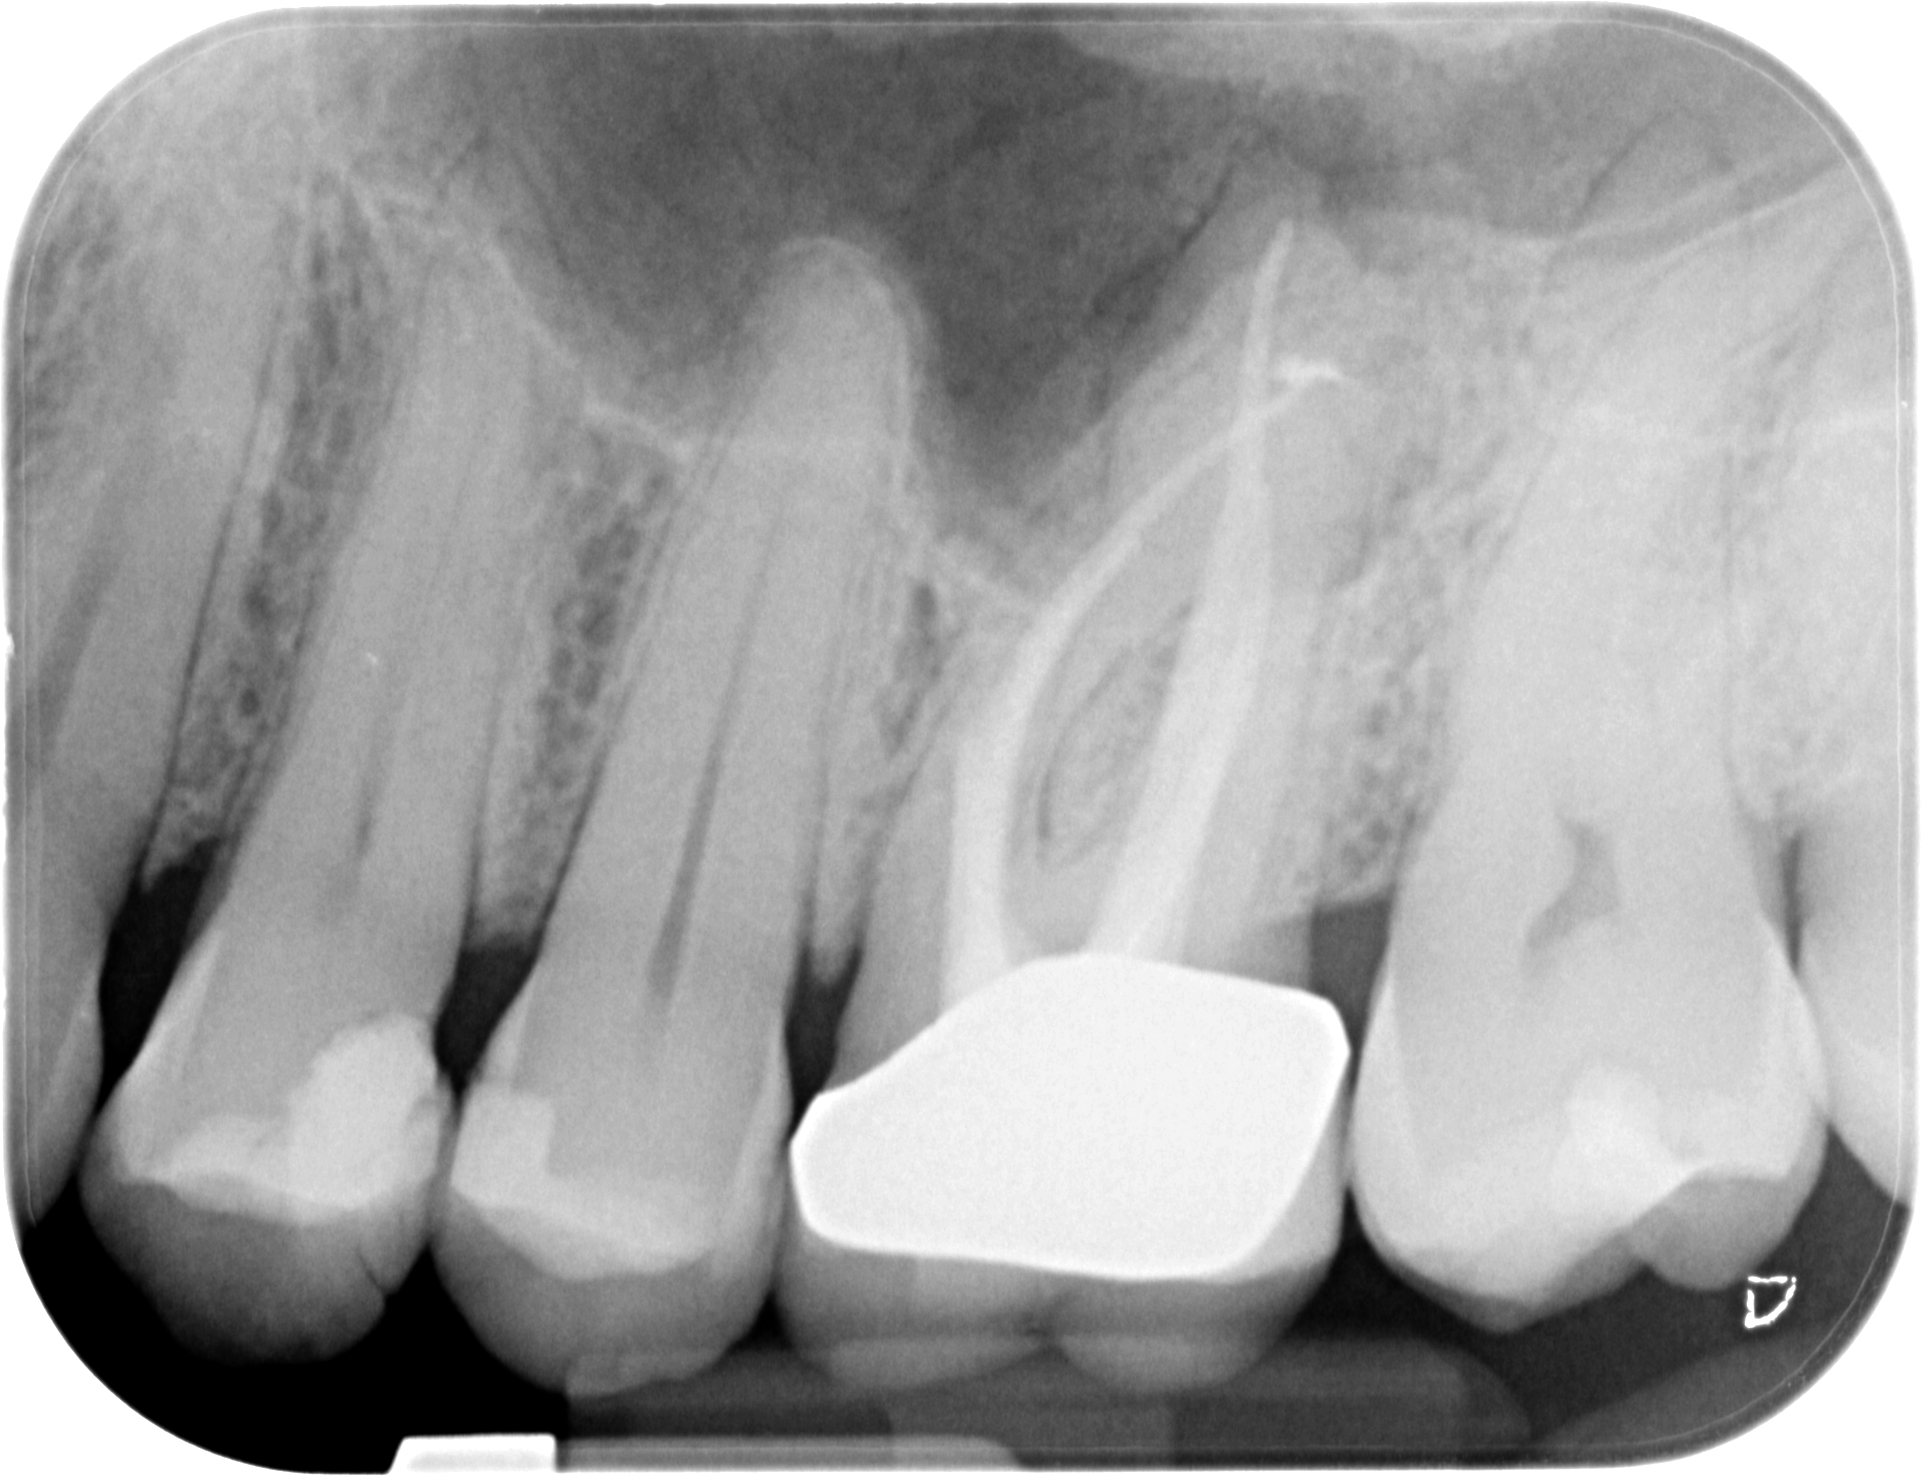

02.03.2020 Patientin DW, geb. am 12.04.1968, Zahn 46, WF Revision, WF-Kontrolle 7 Monate post WF